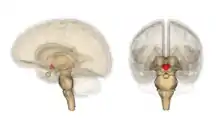

| Hypothalamus | |

- Hypothalamus. Medulla: dorsal nuc. of vagus. - Autonomic dysfunction: temperature; cardiocirculatory; respiratory.

- Hypothalamic lesions may also affect the immune system, which is known in people who consume excessive amounts of alcohol, causing dysplasias and infections.

Lesions are usually symmetrical in the periventricular region, diencephalon, the midbrain, hypothalamus, and cerebellar vermis. Brainstem lesions may include cranial nerve III, IV, VI and VIII nuclei, the medial thalamic nuclei, and the dorsal nucleus of the vagus nerve. Oedema may be found in the regions surrounding the third ventricle, and fourth ventricle, also appearing petechiae and small hemorrhages.[54] Chronic cases can present the atrophy of the mammillary bodies.[55]